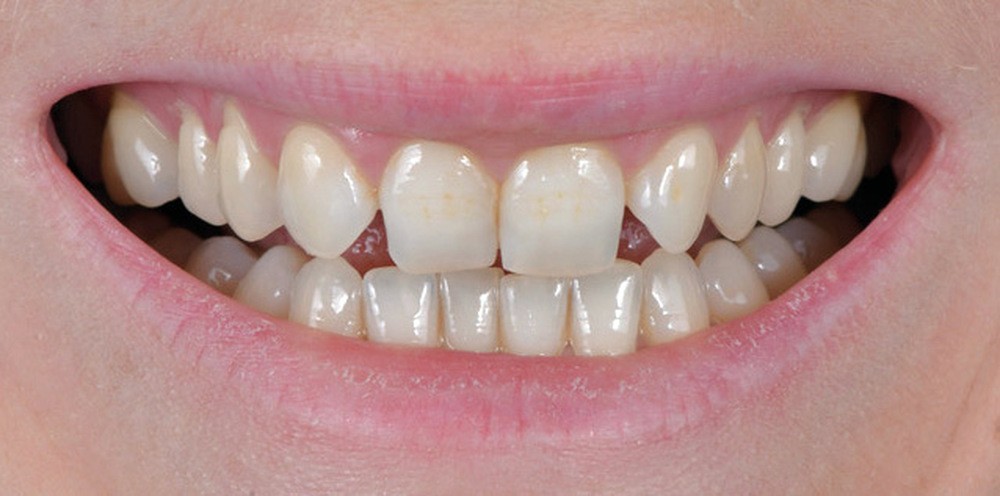

Les Drs Marie Clément et Clara Marcoux aborderont ensuite les différents apports de la dentisterie esthétique aux traitements orthodontiques. Les problèmes de dyschromies isolées ou généralisées, congénitales ou acquises seront développés ainsi que les anomalies de proportions dentaires (dents riziformes…), le maquillage (transformation d’une canine en incisive latérale…) et le remplacement des dents antérieures. Les auteurs présenteront l’intérêt du Digital Smile Design dans le diagnostic et la communication et l’arsenal thérapeutique à notre disposition pour améliorer la satisfaction de nos patients (éclaircissement, traitement des taches de l’émail, composites stratifiés, fig. 9a-d).